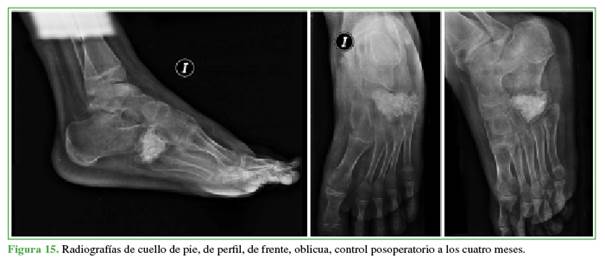

Se permitio el apoyo parcial al mes de la cirugia y comenzar a aumentar la carga, progresivamente, cada semana. El seguimiento se realizó dos veces por mes, los primeros seis meses (Figuras 13-15) y, luego, al año, porque el

paciente no pudo concurrir a los controles por motivos personales (Figuras 16 y 17).